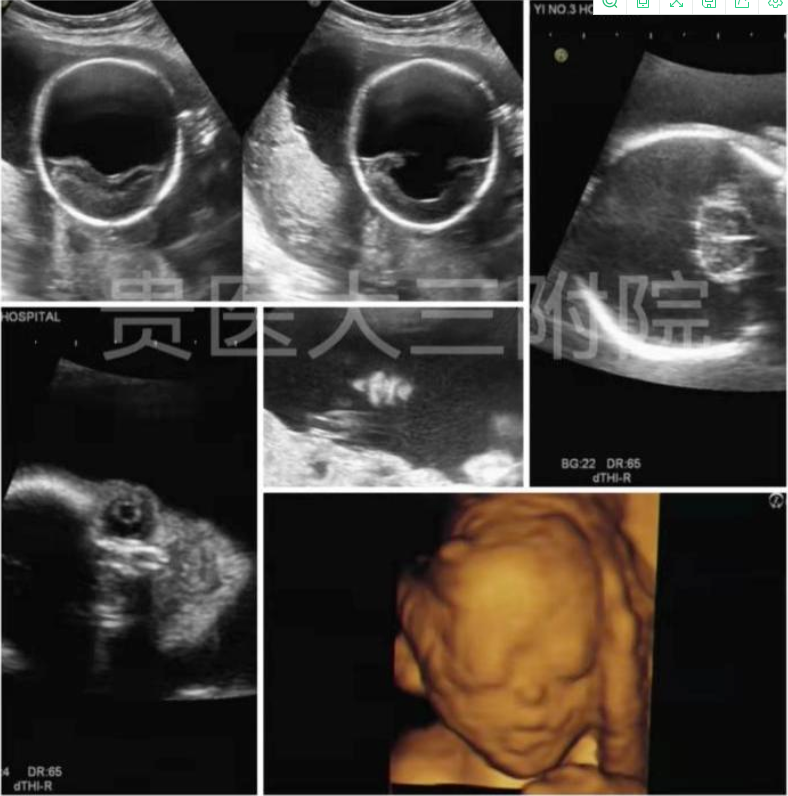

病例3:全前脑畸形(严重脑积水伴颜面部畸形)

胎儿产前超声筛查对于降低妊娠风险、优生优育有非常重要的意义,贵州医科大学第三附属医院超声科将以先进的设备、精准的技术和优质的服务为您宝宝的健康出生保驾护航。